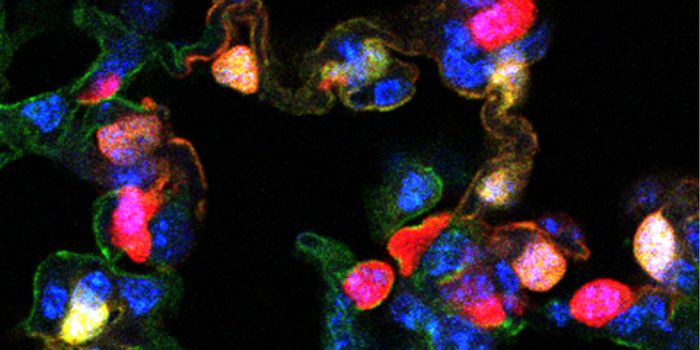

JAN 30, 2024Cell & Molecular BiologyIntroduction Clinical medicine aims to develop novel treatments to fight disease and as a result, must constantly ...